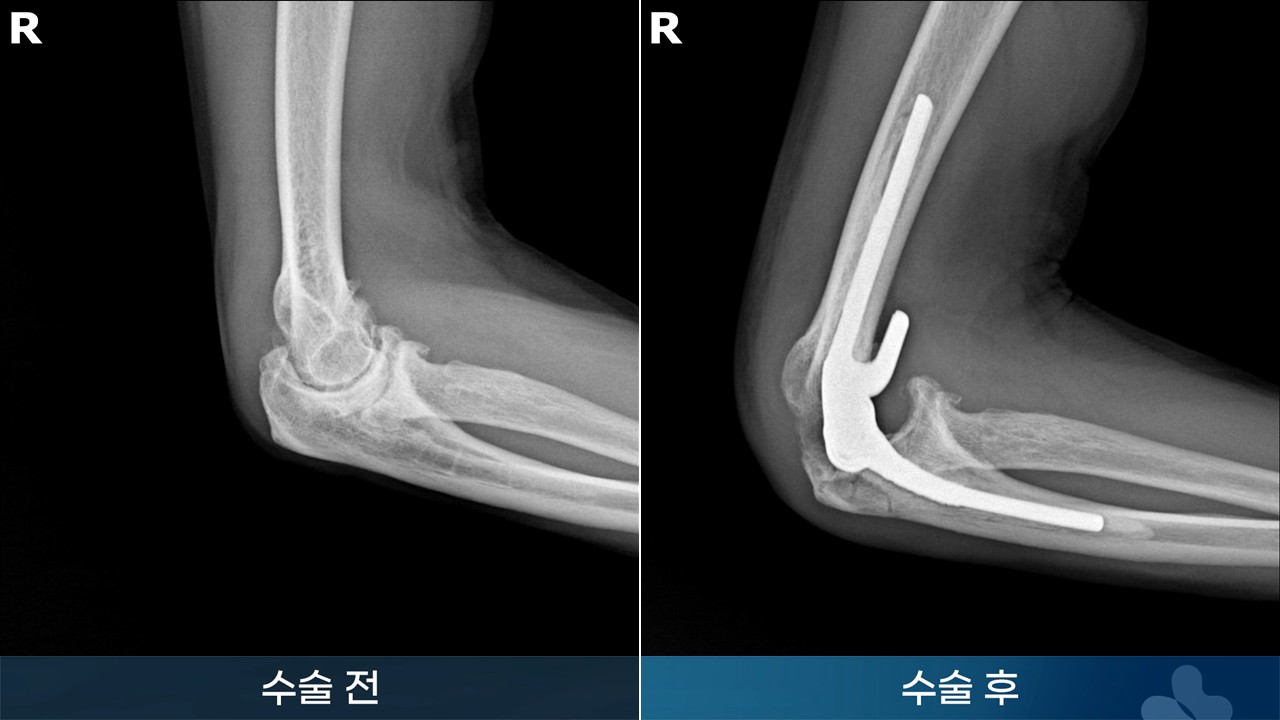

※ 수술 경과는 개인에 따라서 달라질 수 있습니다. 수술 후 멍, 감염, 통증, 부종 등이 발생할 수 있습니다.